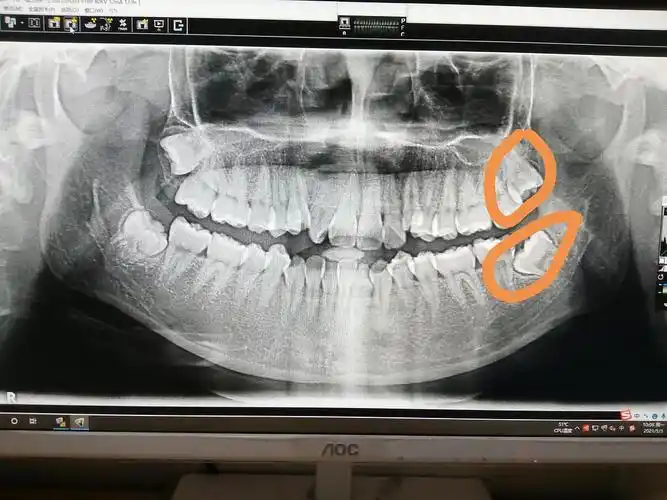

同时拔两颗阻生智齿行吗